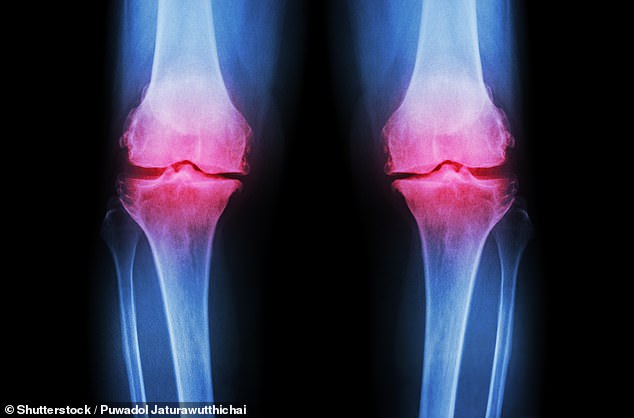

Osteoarthritis occurs when cartilage deteriorates, leading to painful and stiff joints that struggle to repair themselves. Current treatments focus heavily on pharmaceuticals, which can cause side effects like gastrointestinal distress or drowsiness, or on extensive physiotherapy regimens many find difficult to maintain long-term. The study challenges this paradigm by exploring a simple dietary intervention: adding inulin to one's daily routine. This prebiotic fibre feeds beneficial gut bacteria, triggering the production of anti-inflammatory short-chain fatty acids like butyrate, which may reduce systemic inflammation and ease pain perception.